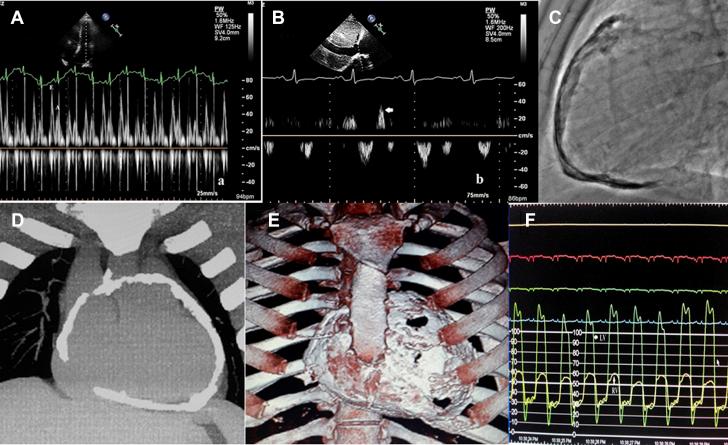

Extensive pericardial calcification is rare in patients with chronic constrictive pericarditis (CCP). We report the case of a young man who had CCP with "eggshell" calcification of the pericardium and the classic features of CCP on echocardiography and cardiac catheterization. The patient had an uneventful recovery following surgical pericardiectomy. ().

广泛的心包钙化在慢性缩窄性心包炎(CCP)患者中较为罕见。我们报告了一例年轻男性患者,其患有CCP,心包呈“蛋壳样”钙化,且在超声心动图和心导管检查中具有CCP的典型特征。该患者在接受心包切除术后恢复顺利。 ()